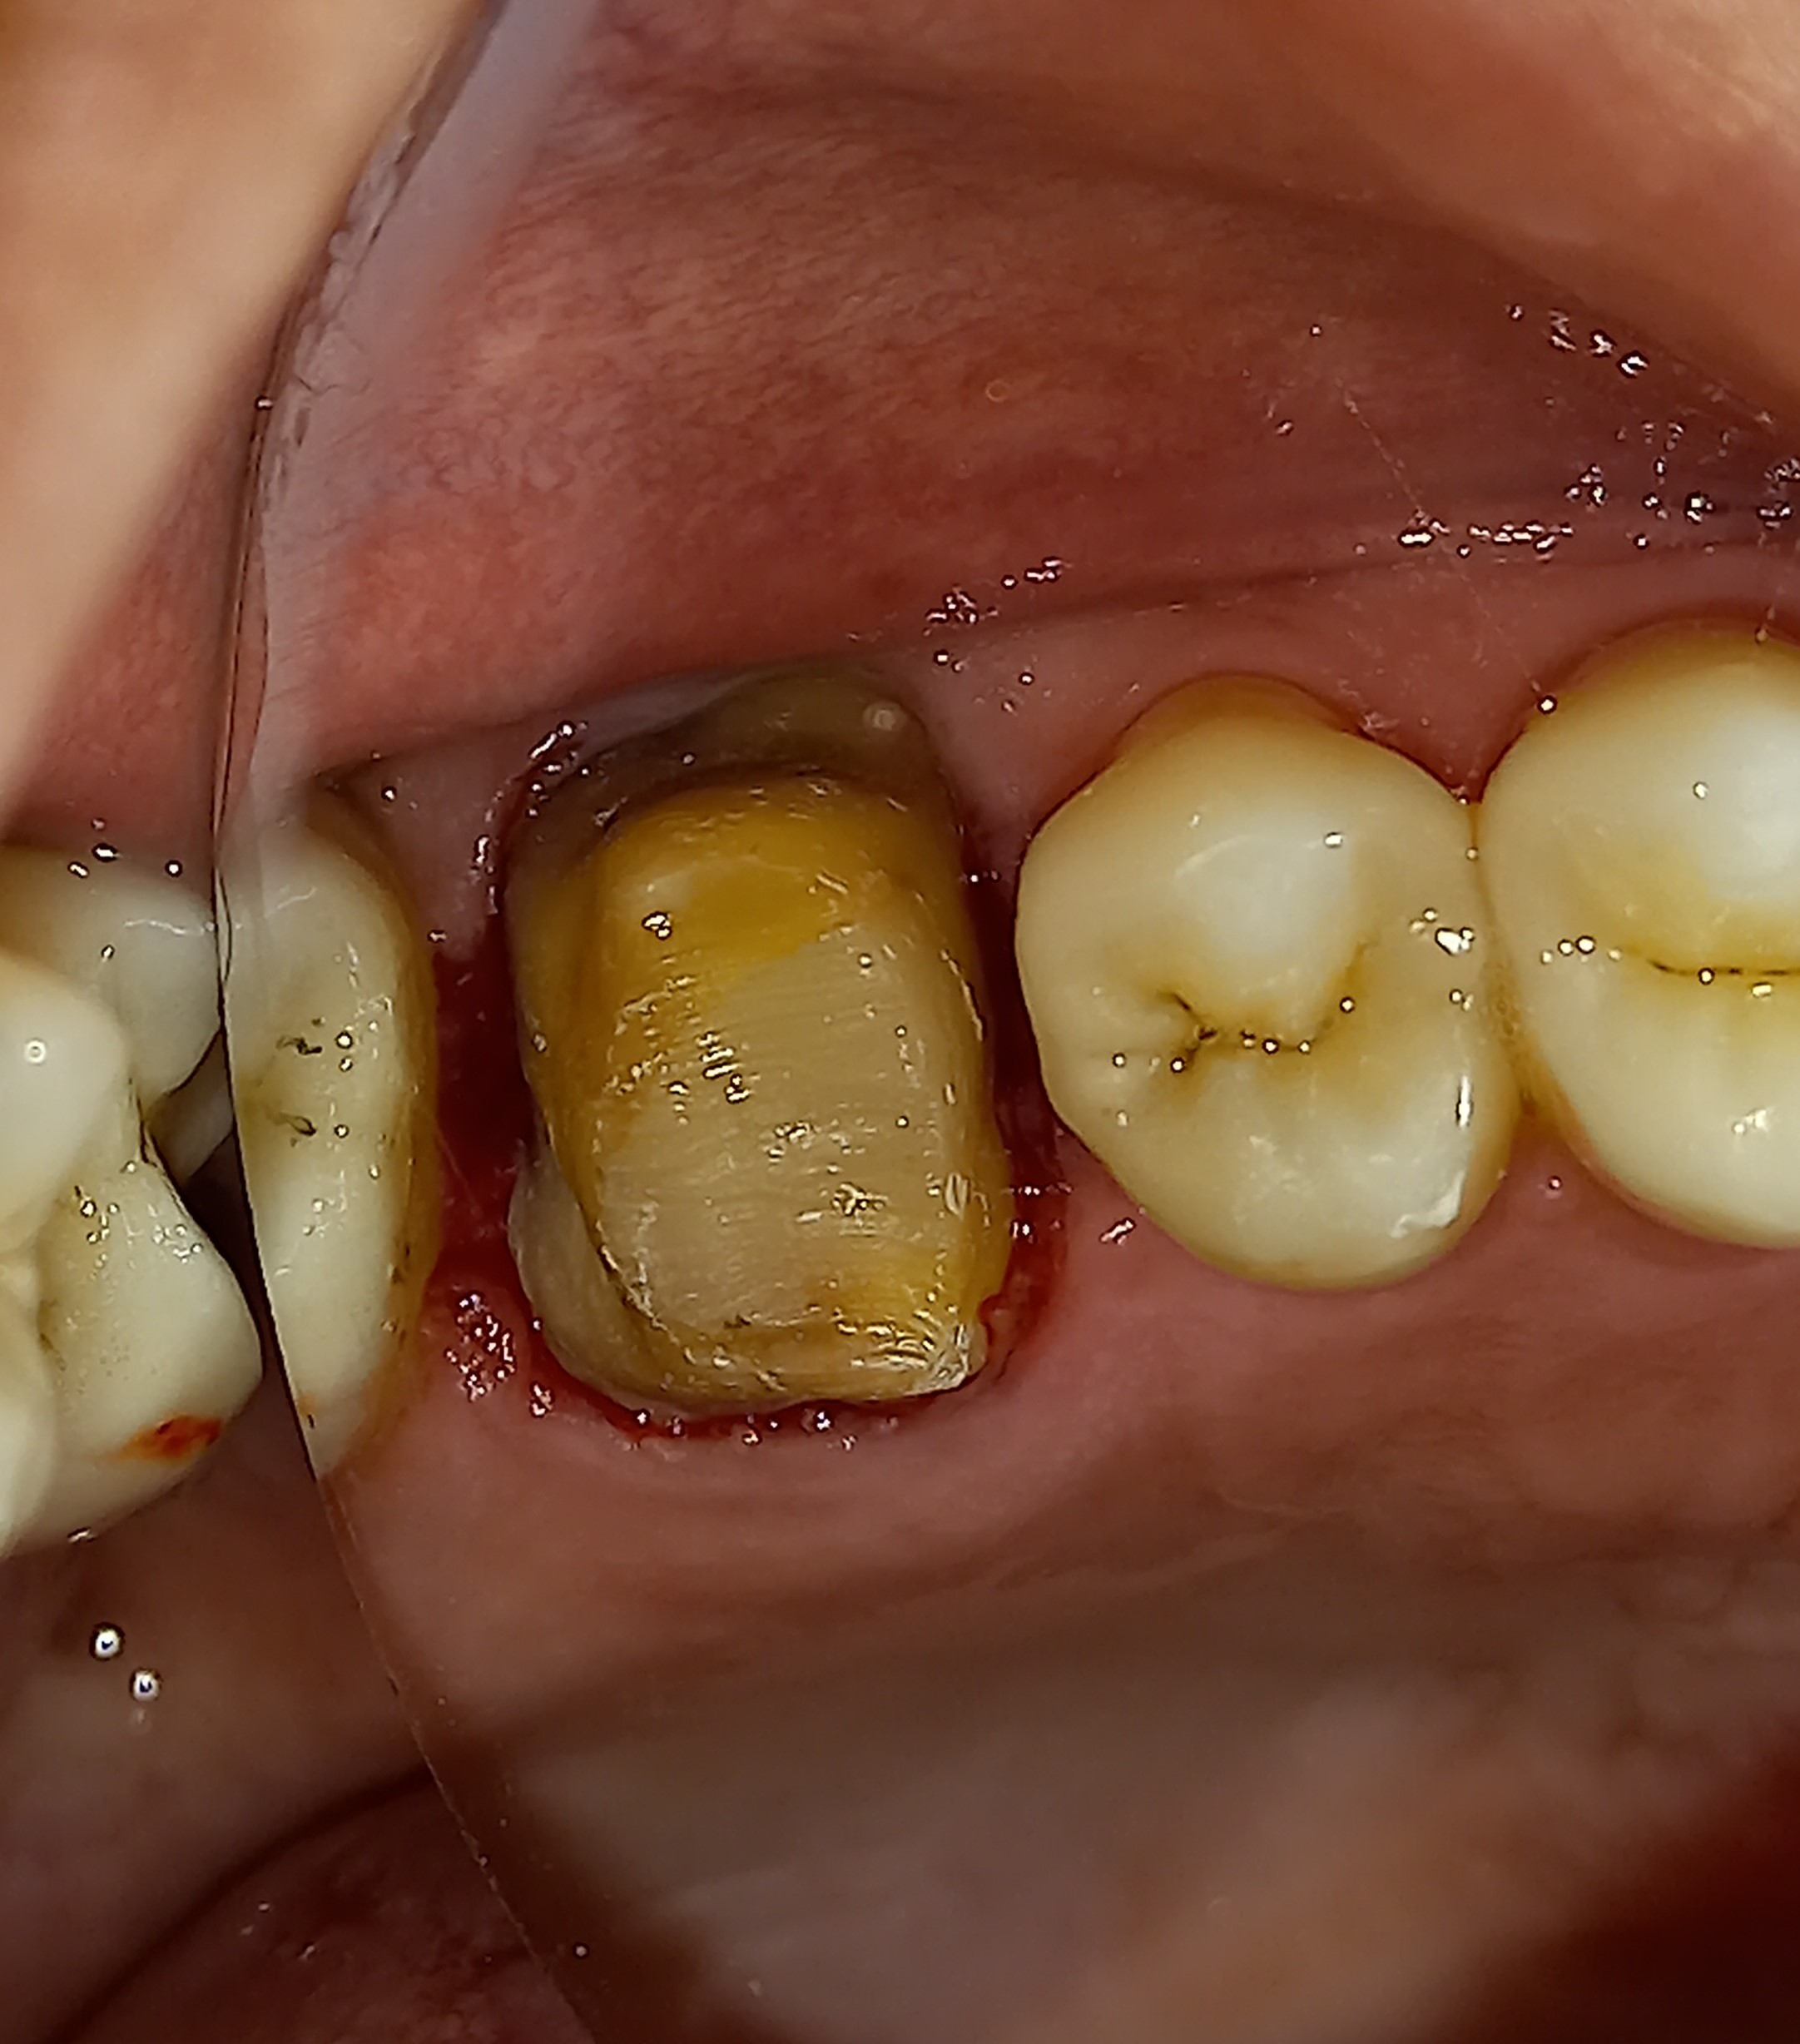

Αρχική κλινική εικόνα του παλιού σπασμένου σφραγίσματος

Εικόνα του δοντιού πριν τη λήψη αποτυπώματος